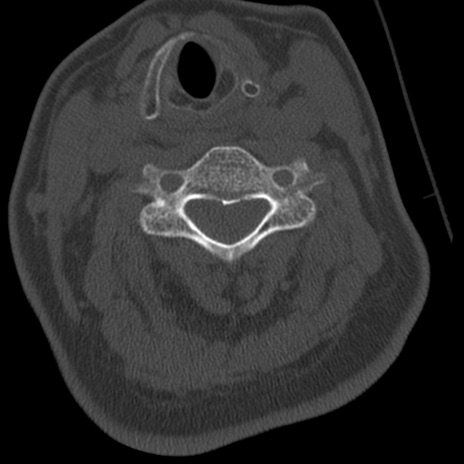

症例50 頚椎CT(横断像)

頚椎CT